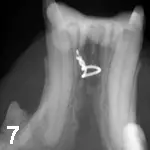

animal was anesthetized for further evaluation of the oral cavity. An open caudal fracture of the left mandibular ramus was visible between the 4th premolar and the 1st molar (Figure B; white arrows). The mandibular artery had been lacerated, and an organized fibrin clot was present (black arrow). An intraoral occlusal view radiograph was taken of the symphysis, and an extraoral lateral radiograph was taken of the TMJ and horizontal ramus of both right and left sides. A 1-cm separation of the symphysis was visible on the films, but no rostral mandibular fractures were present (Figure C). The left lateral film showed a caudal ramus fracture between the 4th premolar and the 1st molar (Figure D). There was no evidence of roots in the fracture site. This film also showed a left craniodorsal TMJ luxation (black arrows) and a left caudal ramus fracture between the 4th premolar and the 1st molar (white arrows).

After alignment and stabilization of the anterior and the posterior portions of the left mandible, the mandibular fracture was then openly reduced. All granulation tissue was debrided from the site, and fracture fixation was accomplished with a full horizontal intraosseous cerclage wire. During tightening of the wire, a small stair-step height discrepancy was noticed between the 4th premolar and the 1st molar, but did not cause malocclusion or trauma to the soft tissue as monitored before and after surgery. The gingiva was then repositioned and sutured. The inside or lingual surface of the caudal cheek teeth (white arrows) was again prepared as above for a lingually placed autopolymerizing composite resin (Figure 6). Intraoral postoperative mandibular occlusal views were taken of the symphysis and the caudal ramus (Figures 7 and 8).